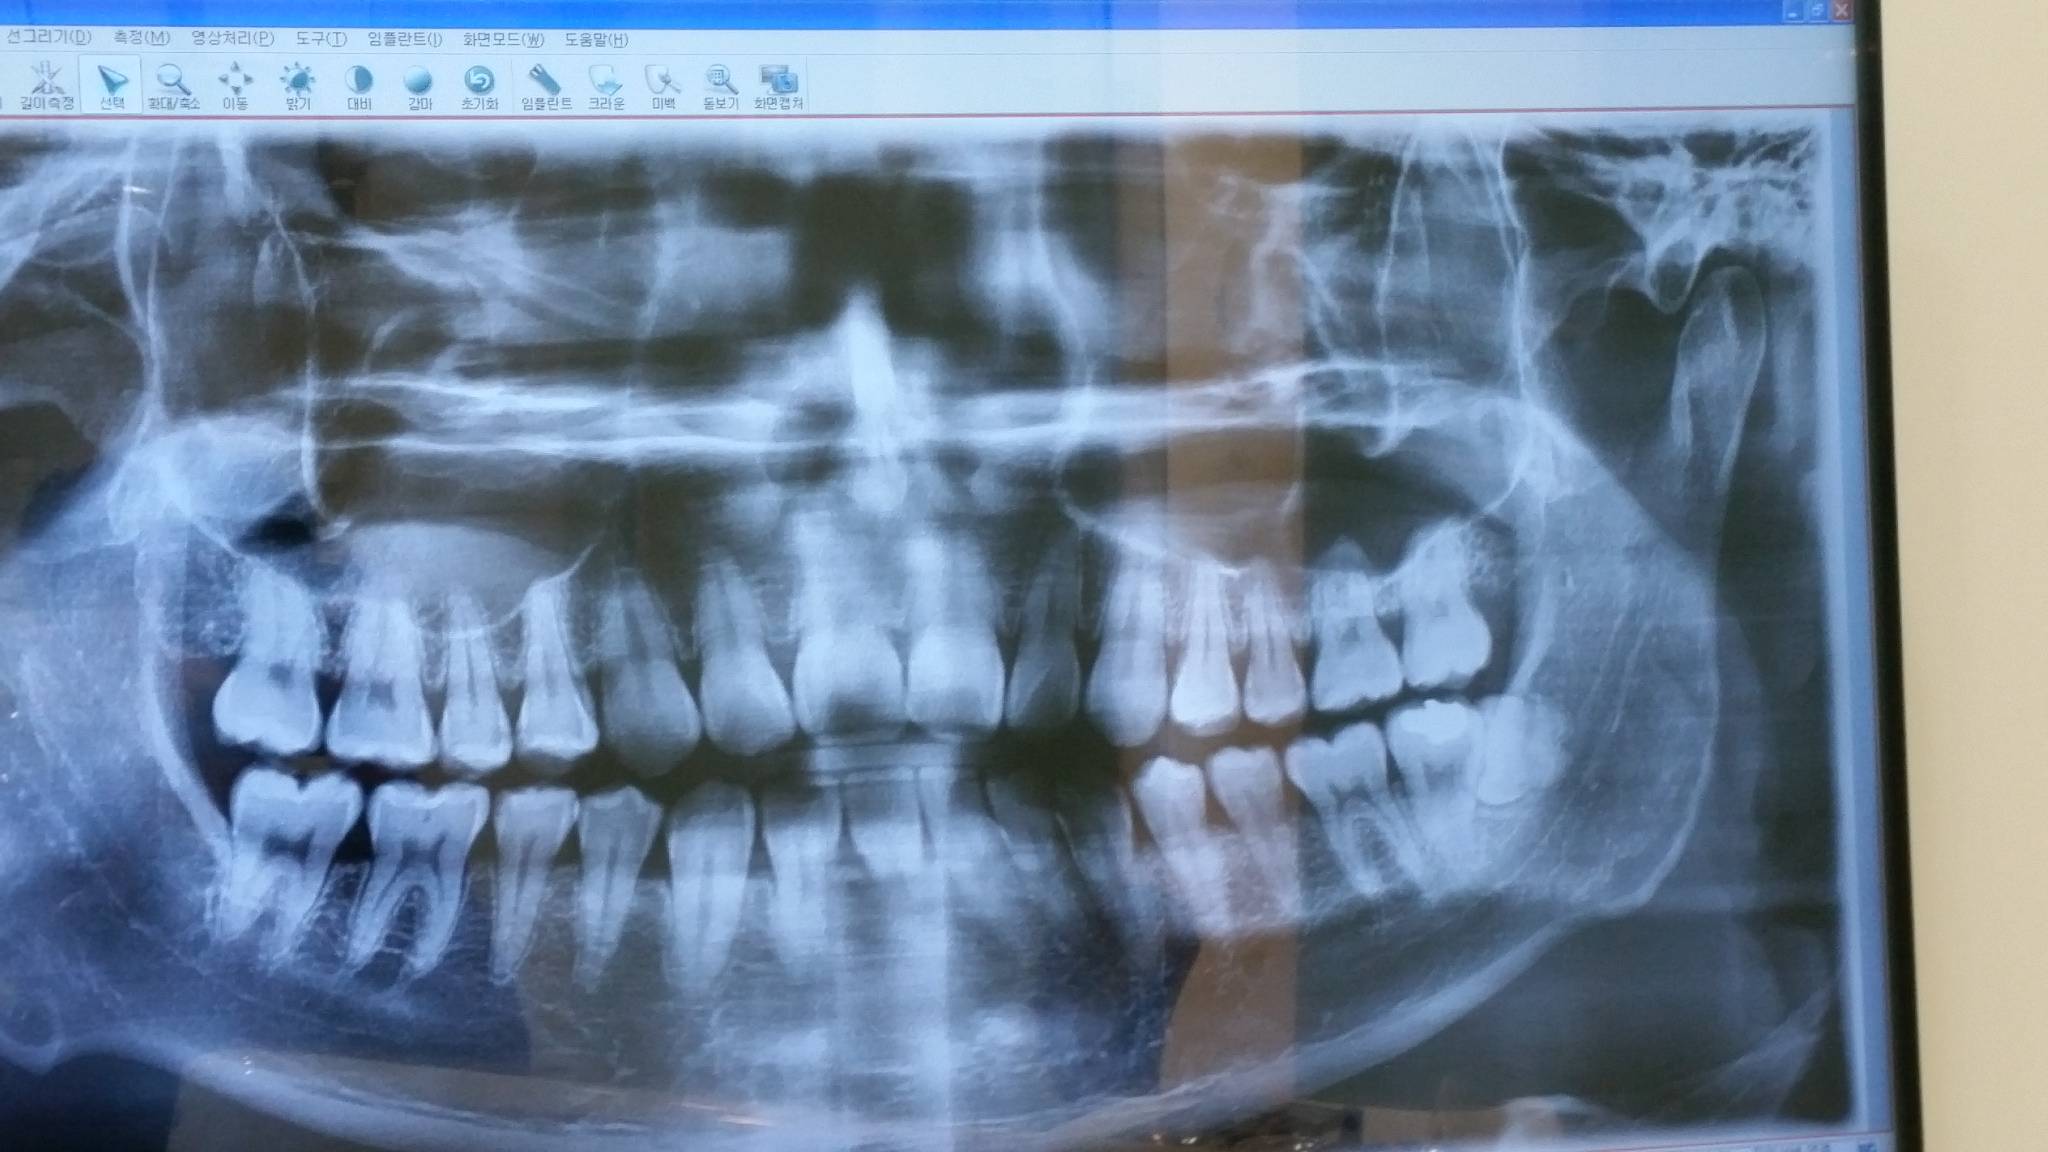

왼쪽 아래 사랑니땜에 치과 갔거든? 일단 두군데 갔음. 처음간곳 A 두번째 간곳 B라 할께

근데 A에서는 X레이랑 CT도 다 찍어보고 알려준거고 B에서는 그냥 X레이만 찍어 보더니 하는 말이었음